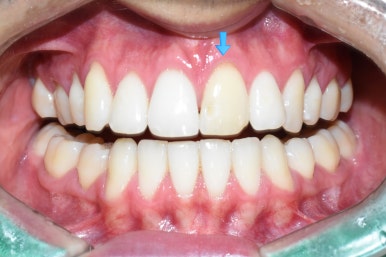

시청역 치과 치료 전 후

전후 비교해보시면 굉장히 자연스럽죠?

일주일만에 어린 외국인 교환학생 환자분이 치아가 완벽해져서 너무 좋아하셨습니다.

깨져있던 부위도 크라운을 하면서 반대쪽과 대칭으로 만들어드렸습니다.

앞니 하나 크라운을 통하여 색깔도 변화 시키고 튀어나온 것도 들어가게 만들 수 있었습니다

미의 기본은 대칭이죠

대문이 하나만 고치고 싶은 경우에

완벽하게 옆 치아와 똑같이 만들기란 쉽지 않습니다